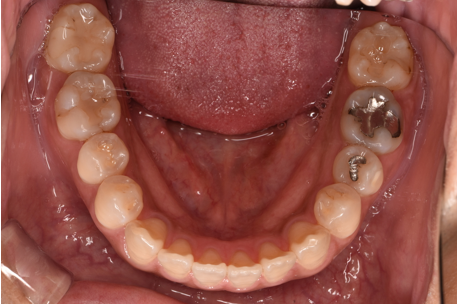

治療前

| カウンセリング・診断結果 | 診察したところ、上の前歯の真ん中に隙間が空いている状態でした(正中離開)。 |